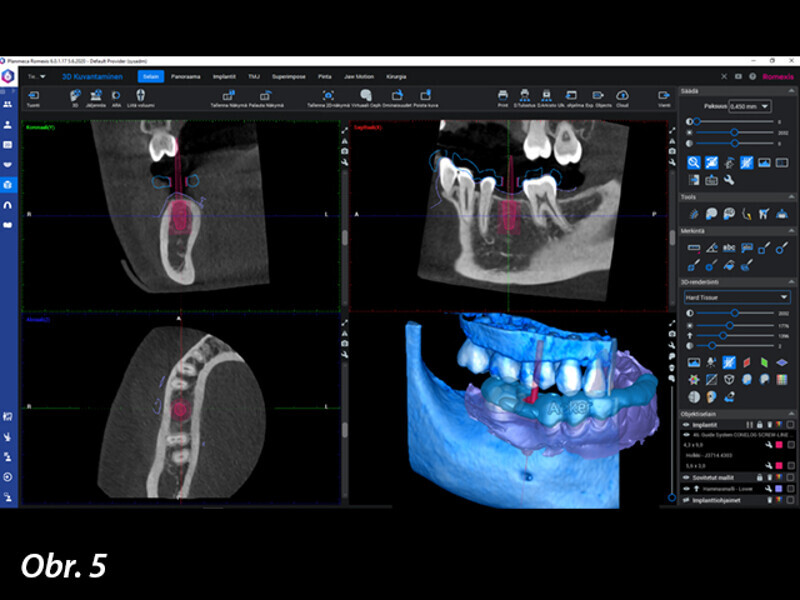

Řízená implantologie za použití řešení Planmeca all-in-one